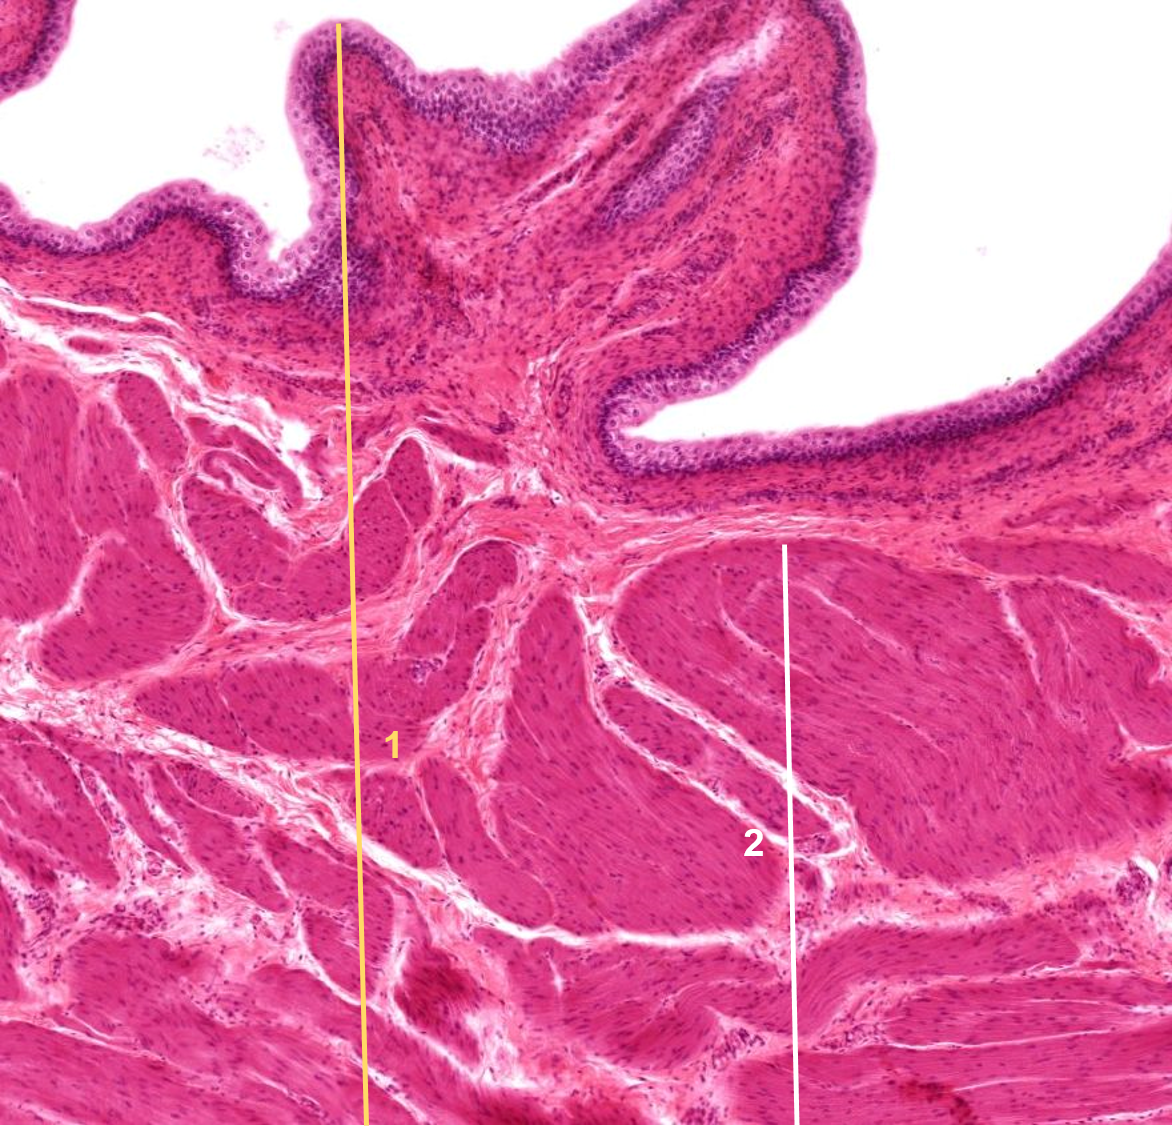

1: Bexiga

2: Camada muscular (músculo liso)